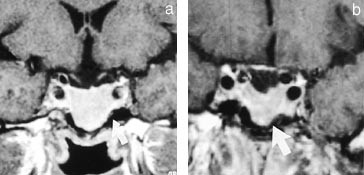

Radiologisk verifisering og kartlegging av tumor skjer fortrinnsvis ved MR-skanning (fig 3). På bakgrunn av sykdommens langsomme utvikling har adenomet ofte en betydelig størrelse og utbredelse ved diagnosetidspunktet, hvilket indirekte sier noe om de somatotrope cellers relativt beskjedne hormonproduksjon. Generelt skiller man mellom svulster som kun har sin utbredelse i sellagropen, såkalte mikroadenomer (<10 mm i diameter), og svulster som i tillegg til intrasellær vekst også vokser ut av sella. Veksten kan skje i ulike retninger – lateralt inn i sinus cavernosus (fig 4), oppover mot de basale cisterner og chiasma og nedover i sinus sphenoidale. De preoperative bilder kan ofte indikere om tumor lar seg radikaloperere, og har derfor stor prognostisk verdi (12, 17, 18).